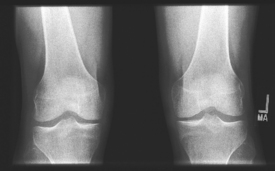

PA axial weight-bearing (Rosenberg method) (S)

PA axial weight-bearing critique